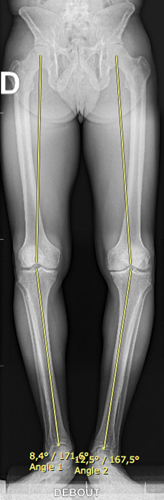

La génétique, l’obésité, les défauts d’axe du membre, les instabilités chroniques, les traumatismes et les antécédents de méniscectomie sont tous des facteurs favorisant le développement de l’arthrose. En effet le ménisque est un amortisseur du genou. Sans celui-ci, l’arthrose évolue plus rapidement.

Le bilan comprend des radiographies standards en charge, une goniométrie pour mesurer l’axe mécanique.

- 3 mois avec Rx et goniométrie.